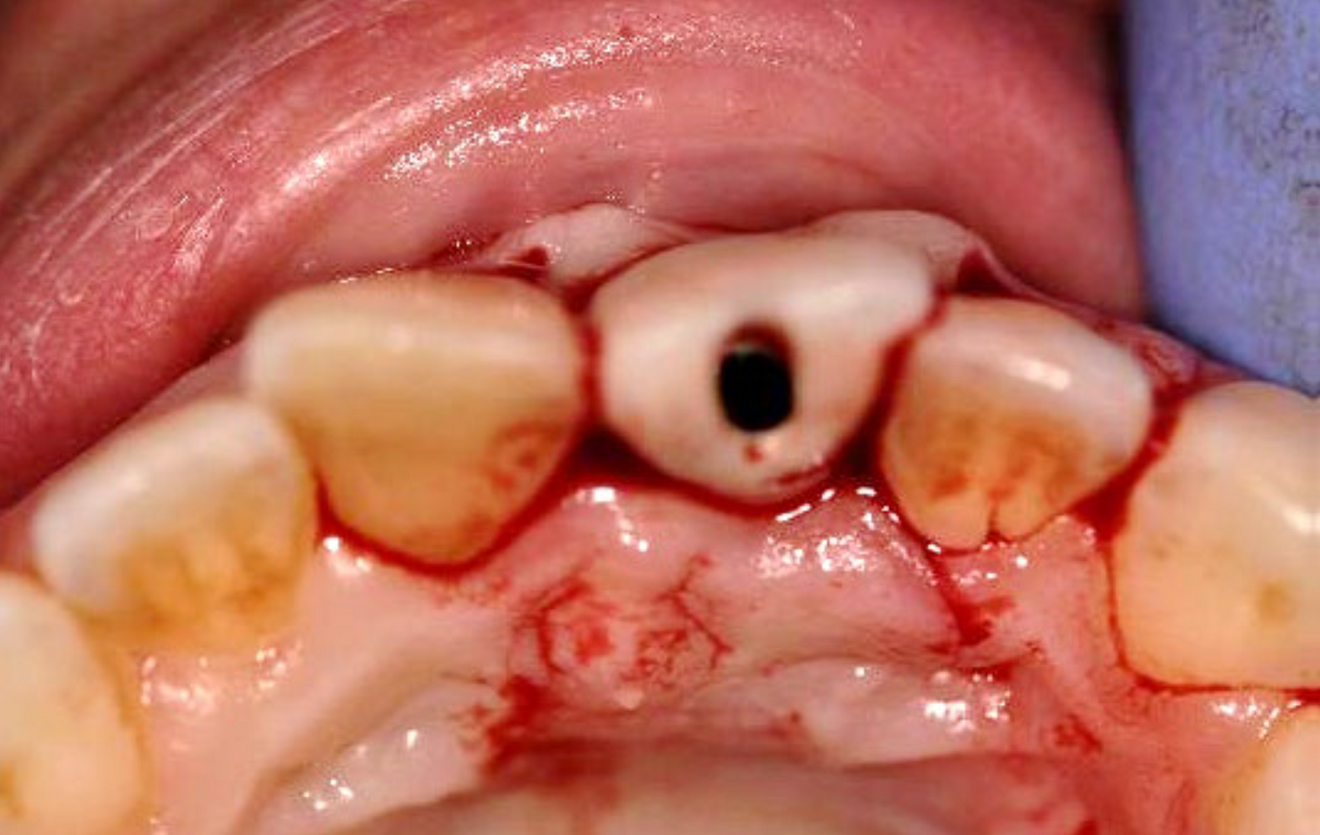

Immediate temporary crown (c) ...

... and intra-oral view 32 weeks post-op (d).